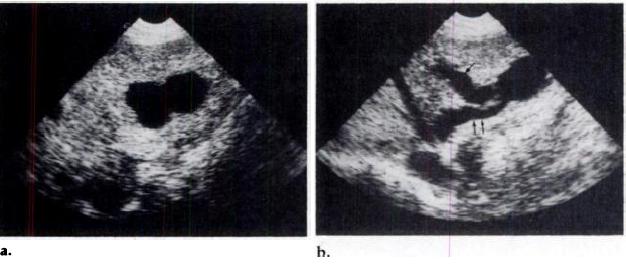

Ultrasound (US) examination (Fig.la, ib) showed a bilocular aneurysm in the lateral segment of the left hepatic lobe; it communicated with the left portal vein and the left hepatic vein. The hepatic artery was also dilated. Celio-mesentenic angiognaphy (Fig.2a, 2b) confirmed these findings and also showed poor opacification of theright portal vein. Percutaneous aneurysmal occlusion using a 27-mm balloon

Figure 1. Case 1. Transverse sonograms demonstrate biloculate aneurysm (a) in the

lateral segment of the left hepatic lobe. It communicates with the left portal vein (single

arrow) and the left hepatic vein (double arrows) (b).

Figure 2. Case 1. Celio-mesentenic angiognaphy shows dilatation of the hepatic antery

and its tortuous branches (a); in the venous phase (b), the dilated left portal vein

(single arrow) feeds the fistula, which also communicates with the dilated left hepatic

vein (double arrows).